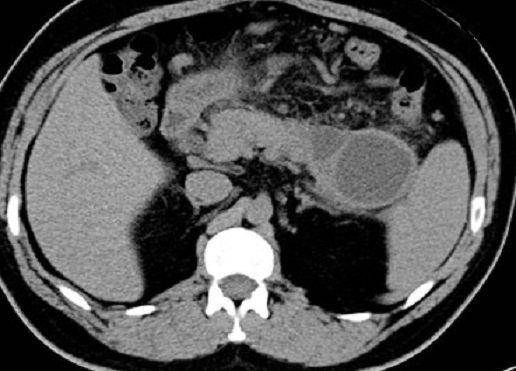

Image TDM en coupe

axiale d'une pancreatite chronique en forme

laculaire isodense avec images de pseudokyste a

hypodense a densite inferieure de 20 UH situe au queue du pancreas |